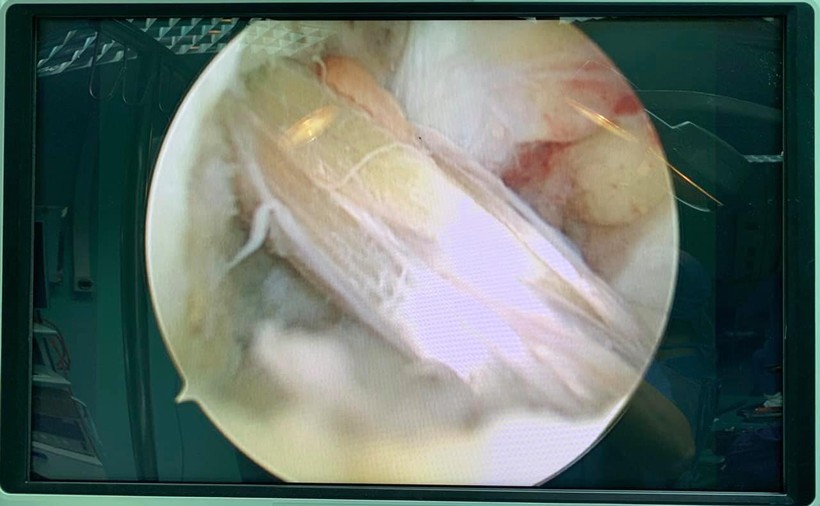

Qua thăm khám, các bác sĩ nhận thấy gối phải bệnh nhân lỏng, test Lachman, test ngăn kéo trước trên MRI phát hiện có hình ảnh đứt hoàn toàn dây chằng chéo trước khớp gối. Bệnh nhân được chẩn đoán đứt dây chằng chéo trước khớp gối và đã được phẫu thuật nội soi tái tạo dây chằng bằng phương pháp All Inside.

| Hình ảnh đứt dây chằng chéo trước của bệnh nhân trên phim MRI. Ảnh: BVCC |